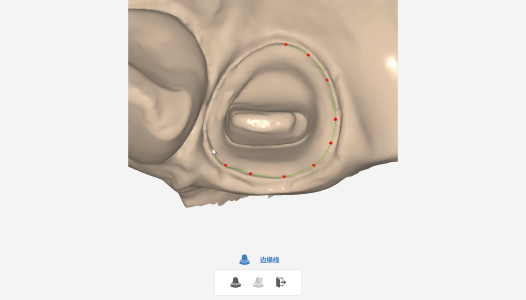

| Draw edge lines

|